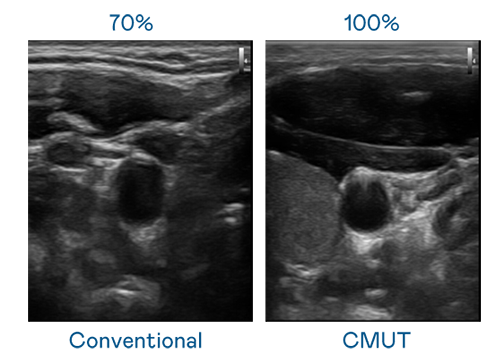

CMUT 技术是一种用电容式微机电元件来产生超音波讯号的技术。与传统 PZT 压电式技术相比,CMUT 频宽增加 30%,更宽频的超音波讯号让影像解析度大幅提升,是实现高影像品质医疗超音波扫描、促进精准医疗发展的关键技术。

大频宽带来超清晰影像

超音波影像的解析度高低,首先取决于探头能发出的讯号频宽。亿万28 CMUT 可提供高清晰的超音波讯号,提供高频宽、高灵敏度、影像纹理细节更高的超音波影像,协助医护人员缩短影像判读时间及利用精准的医疗影像进行诊断。